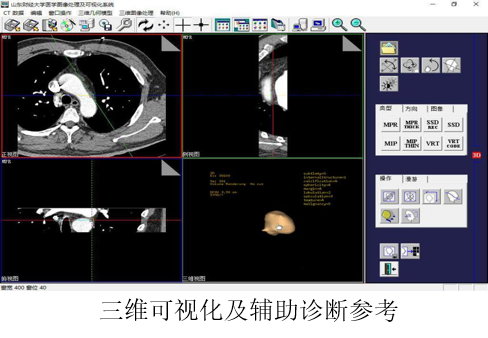

模糊聚类及表示学习在肺部肿瘤辅助诊断中的研究与应用

目前,利用CT数据进行肺结节/肿瘤的自动提取与辅助诊断对于临床早期肺癌的诊疗意义重大。为了有效提高诊断结果的可重复性和对于图像、疾病解释的一致性,课题组研发了该系统,满足了肺部病灶区域分析及辅助诊断、符合医生操作习惯的实时功能需求,在医学图像去噪、超分辨重建、病灶区域分割及三维可视化、矩阵快速求解及优化等关键技术方面取得了理论创新和关键技术突破。

系统已经在山东省千佛山医院、山东省医学影像学研究所、烟台毓璜顶医院等十余家医院及科研院所推广应用,有效地辅助临床医生对病灶组织进行定量乃至定性分析,经济/社会效益显著,获得山东省科技进步一等奖。系统研发工作得到了国家自然科学基金、山东省重点研发计划的支持,相关成果获得授权发明专利5项、软件著作权8项、发表学术论文22篇。